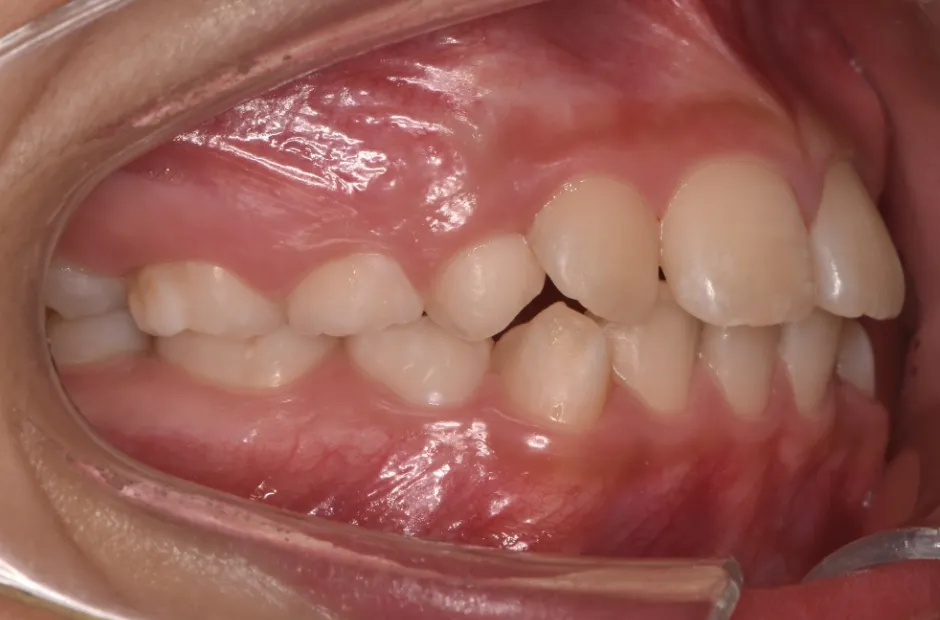

反対咬合

| 診断名・主訴 | 前歯反対咬合 |

|---|---|

| 年齢・性別 | 12歳・男性 |

| 治療期間・回数 | 1年半 18回 |

| 治療に用いた主な装置 | リンガルアーチ(前方誘導弾線) |

| 抜歯部位 | なし |

| 治療費 | 35万円(税抜) |

| リスク・副作用 | 装置による違和感・疼痛・歯肉退縮・歯根吸収・虫歯のリスクなど |